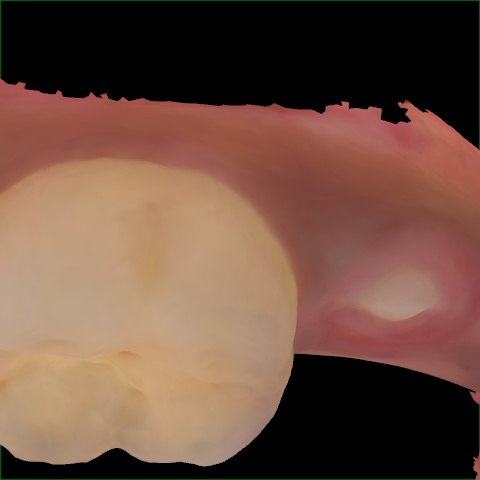

Annotated as "Good"